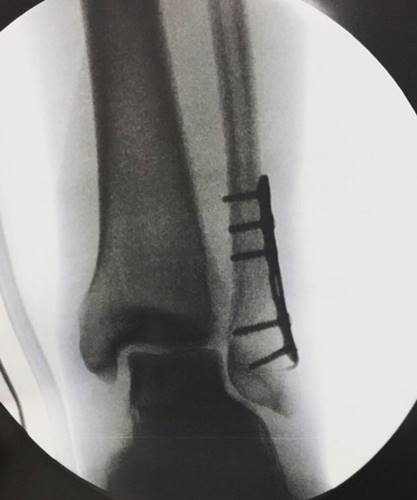

Fabio Assunção usou seu Instagram para falar que está bem, após cirurgia no pé e afastar os rumores que esteja com problemas pessoais. O ator escorregou e acabou fraturando o pé esquerdo, onde teve que colocar uma placa com pinos.

“Escrevo a vocês, desses fã clubes dedicados. Escrevo aos curiosos, aos amigos, aos remetentes de tantas mensagens e até aos desinteressados, sem filtro. Como dizem, o que não mata fortalece. Quero dizer, de próprio punho, como sempre, que não há motivos para preocupação ou dúvida – o alimento da especulação. Já havia durante a novela ou melhor, antes da nossa estreia (??!!) rumores de pessoas muito insatisfeitas, jogando contra escrevendo sobre faltas inexistentes. Gravo desde o inicio numa queda de braço entre o que é escrito aleatoriamente e o que está no ar, todos os dias. Previram minha morte, a morte da minha personagem mas o fato é que minha energia, fruto da troca com uma centena de profissionais, meus parceiros, está no ar e isso é inegável. Tive apenas esse ano, em dois meses e meio três cirurgias na mão, fruto de uma ruptura no tendão do polegar esquerdo e esta madrugada, após gravar ontem, uma quarta cirurgia, dessa vez na base do pé esquerdo onde coloquei uma placa com pinos, gesso para que eu termine a novela em maio cumprindo a demanda da trama de Totalmente Demais e siga sem sequelas meu ofício. Portanto, à vocês, meu muito obrigado pelas mensagens. Nunca houve nem está havendo nenhum plano do Arthur deixar a novela. Quem escreve isso por aí não consegue me desviar do meu foco e estou bem!!!! Vamos até o fim, em paz, respeitando as determinações desse poder superior e usando nossa força para continuar. Conheço o joio e escolho o trigo. Nosso sucesso e dedicação, de todos dessa novela, estão à disposição de todos diariamente. Muito amor à todos”, escreveu ele, postando uma foto de seu Raio-X.